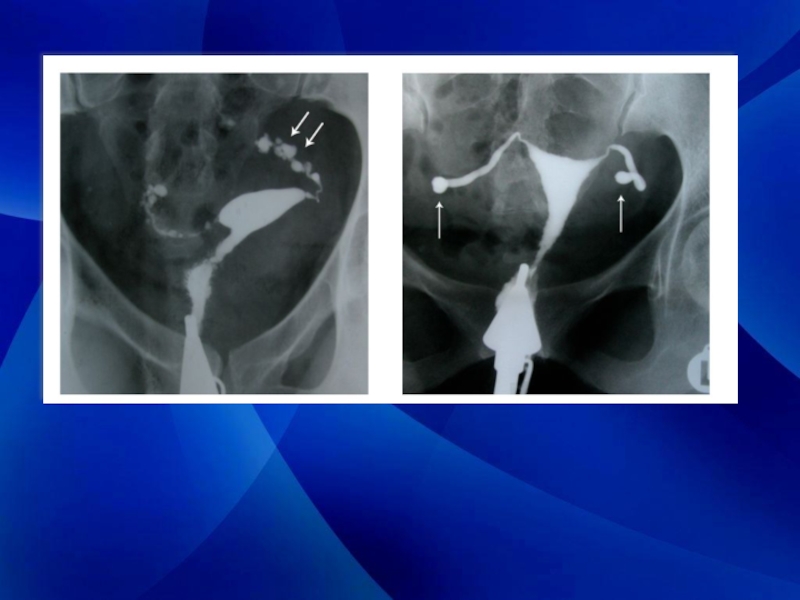

Гистеросальпингография